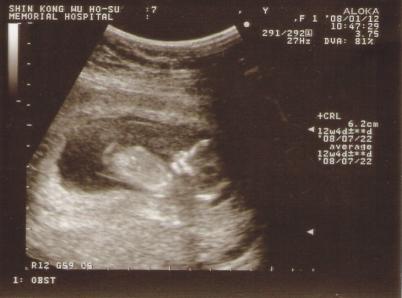

這次的產檢猴爸爸有陪我進超音波室唷! 在照的時候,哆哆的姿勢是趴著的 是超音波室的小姐把影像反過來拍 ... (詳全文)

發表時間:2008-01-14 10:09:46 | 回應:0